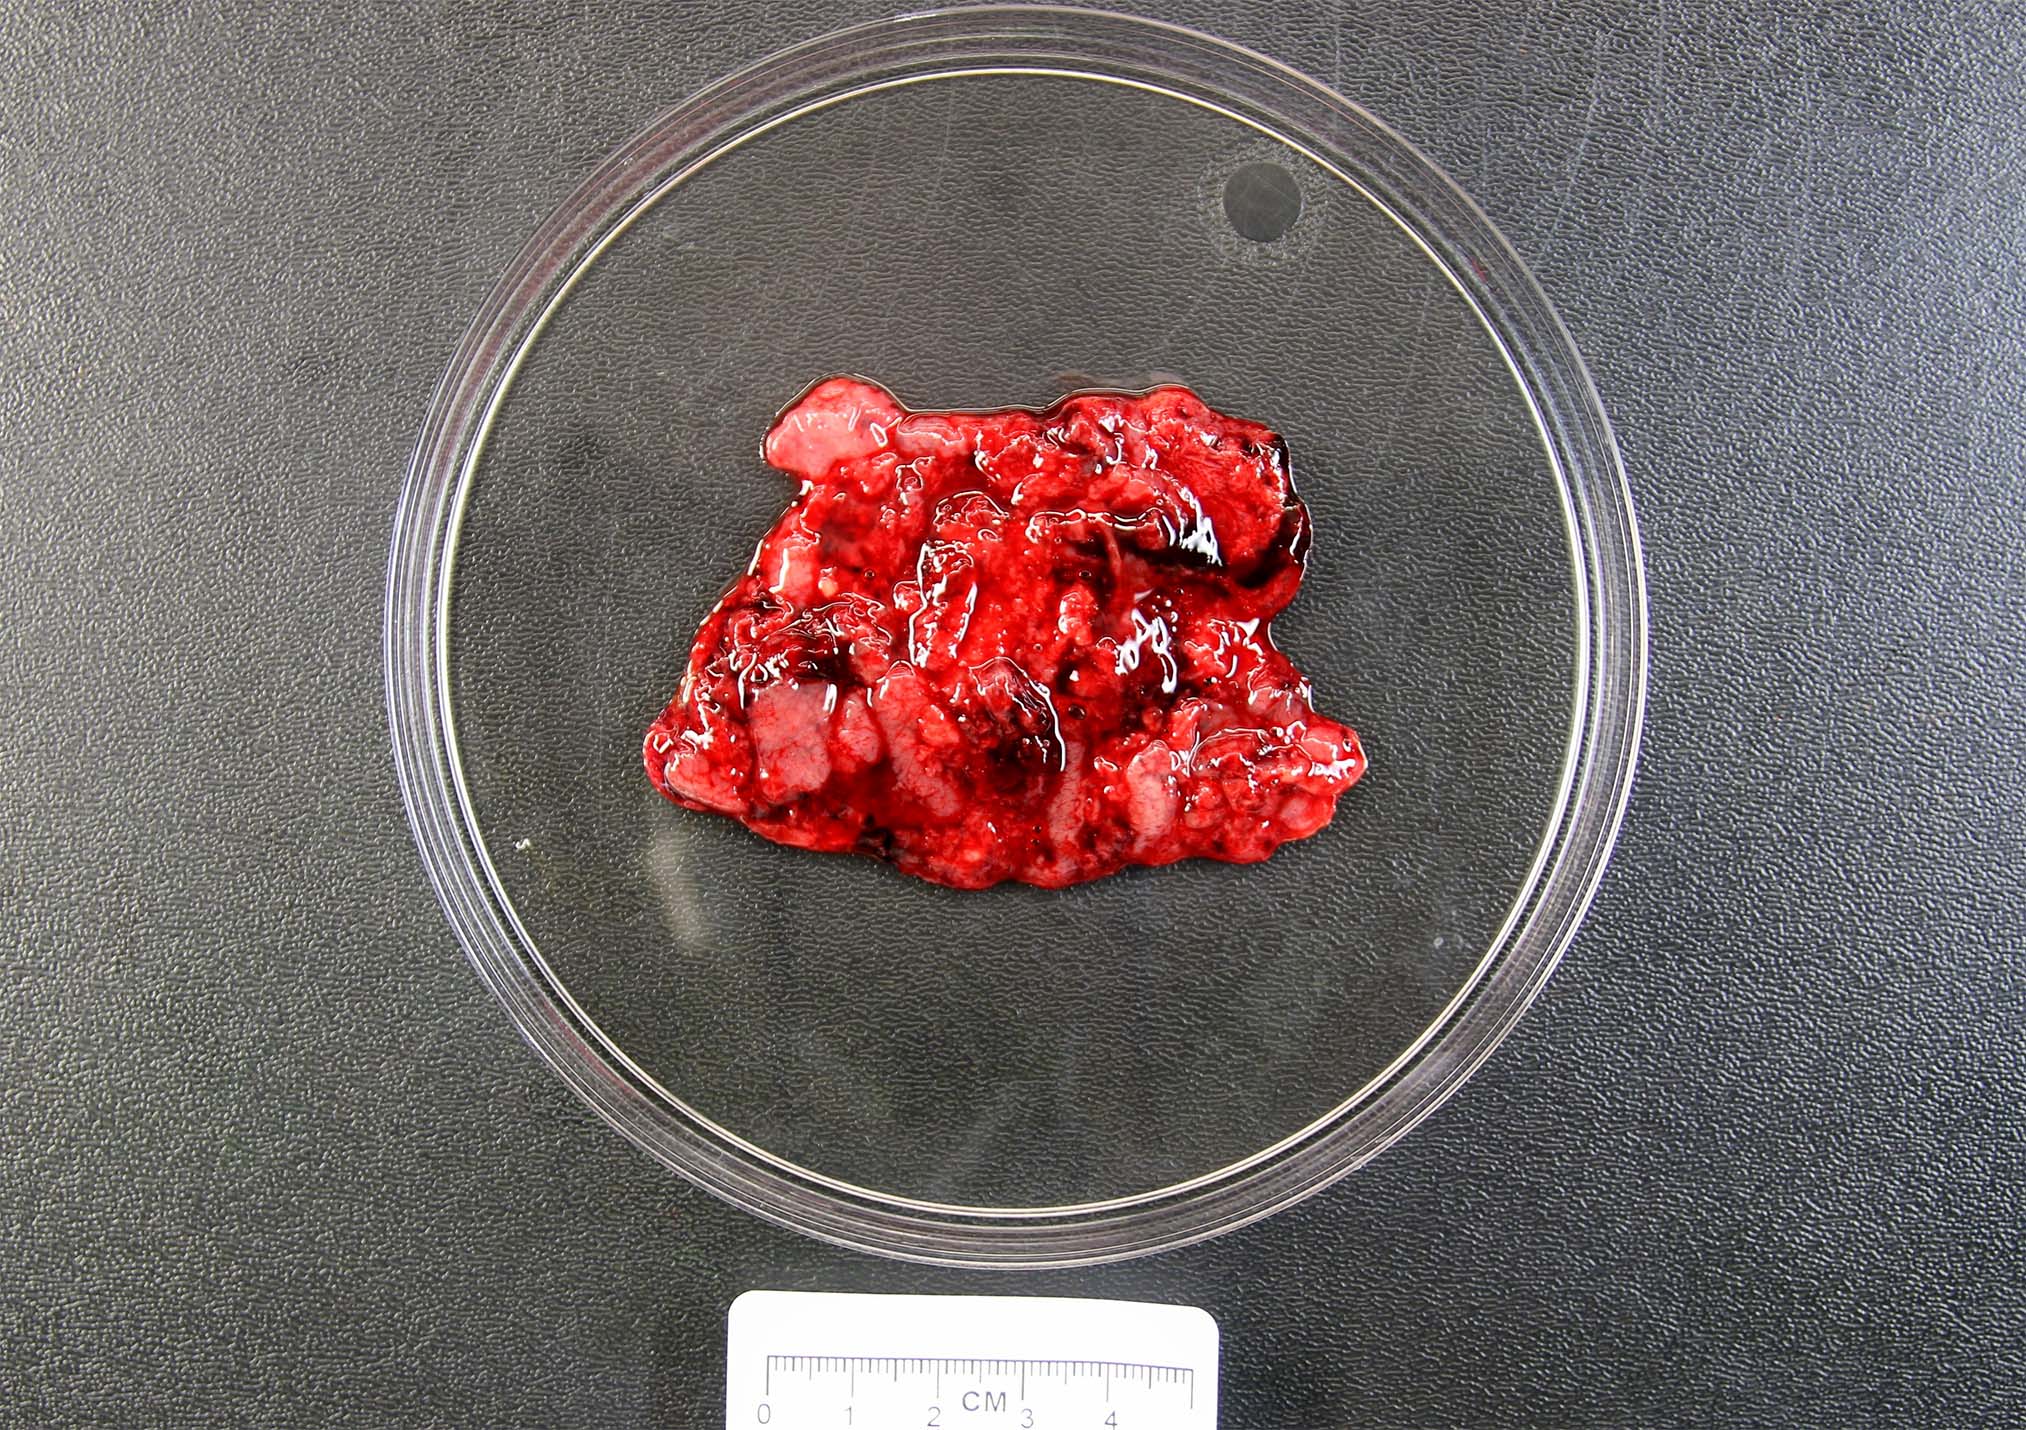

Gross description

- Specimen often consists of fragments of placental tissue (chorionic villi, membranes / gestational sac that may be intact or disrupted and decidua)

- Despite identification of embryo or fetus on ultrasound, an embryo is often not identified / recognized in surgical specimens (J Clin Pathol 1981;34:819)

Gross images